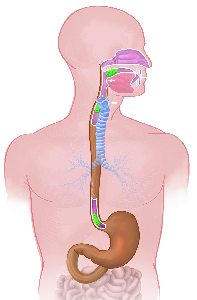

Über 860 Stichworte mit 120 Illustrationen auf 400 Seiten machen aus dem Lexikon der Lunge ein

wertvolles Werk.

Detailreiche Fotografien aus der medizinischen Praxis ergänzen die Texte; moderne, genaue,

wissenschaftliche Zeichnungen geben Einblick in die Anatomie und die Funktion der Lunge und

anderer Organe.